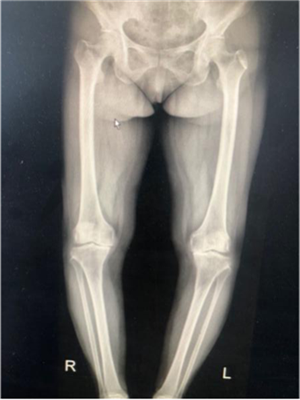

?。ㄊ中g(shù)前、手術(shù)后對(duì)比)

5月29日,徐阿姨如期進(jìn)行了雙側(cè)全膝關(guān)節(jié)同期置換術(shù)。術(shù)中發(fā)現(xiàn)徐阿姨膝關(guān)節(jié)退變嚴(yán)重,有大量的滑膜軟骨瘤,清除病變后又發(fā)現(xiàn)她前交叉韌帶缺失后交叉韌帶纖細(xì),即決定采用限制性較高的E1 AS墊片,該假體極大的提高了手術(shù)安全性,降低了手術(shù)風(fēng)險(xiǎn)和創(chuàng)傷,手術(shù)歷時(shí)2小時(shí),患者術(shù)后恢復(fù)良好。手術(shù)后第二天,徐阿姨就可以扶著助步器下地活動(dòng),目前已可以徒步行走、上下樓梯。